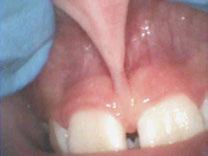

Over 10 years ago, we began Orthotropic® treatment for a 5 year, 3-month-old boy with a diagnosis of Pierre-Robin Sequence, Obstructive Sleep Apnea (OSA), and Failure to Thrive (Figure 1). With lack of forward development of the face com-

12 Pediatric Dental Practice US Volume 1 Number 1 PEDIATRIC PERSPECTIVE

monly seen in Pierre-Robin patients, his airway was compromised, resulting in OSA. The Failure to Thrive diagnosis likely resulted from insufficient growth hormone being released during the deeper stages of sleep. This treatment began before any permanent teeth erupted. Our goal was to eliminate OSA.

Orthotropics® uses removable appliances to laterally expand the upper arch while simultaneously advancing the upper anterior teeth to their proper place in the face. Then the mandible is developed forward. Orthotropics® is my preferred treatment in cases like this because it negates the head gear-effect producing better facial balance5 and also can result in substantial airway improvements (Figure 2).6

Figure 1: Pretreatment gallery Figure 3: Today, he’s a tennis player Figure 2: Pre- and posttreatment airways